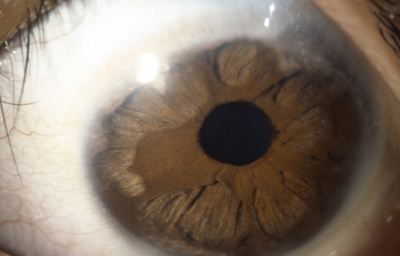

Anomalias del Estroma: Hiperplasia, Hipoplasia

Hipoplasia

Archivo fotográfico Dr. Francisco Barraquer.